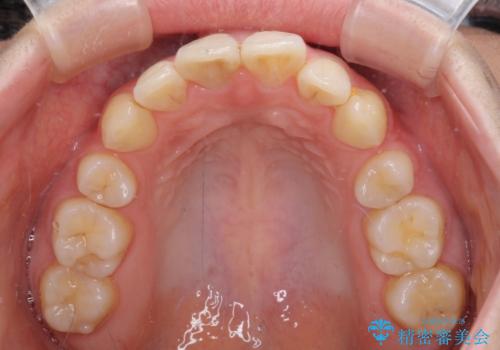

ただし、長期間欠損を放置していたことで、咬み合う上の奥歯が動いてしまっていたので、まずは上顎奥歯の部分矯正を行い、より理想的な咬み合わせを目指すこととしました。

右下の歯は、レントゲン上歯髄組織まで虫歯が及んでいるように見えましたが、痛みの症状は強くなかったため、歯髄組織の一部を断ち歯根部分の組織を保存する生活歯髄療法を第一選択に処置を進めて行くこととしました。

まず生活歯髄療法を行い、その後部分矯正やインプラント処置を行いましたが、最初の処置から1年以上経っても右下奥の処置歯の神経組織に異常は認められませんでした。

部分矯正を行ったことで、違和感のない咬み合わせを達成することができました。